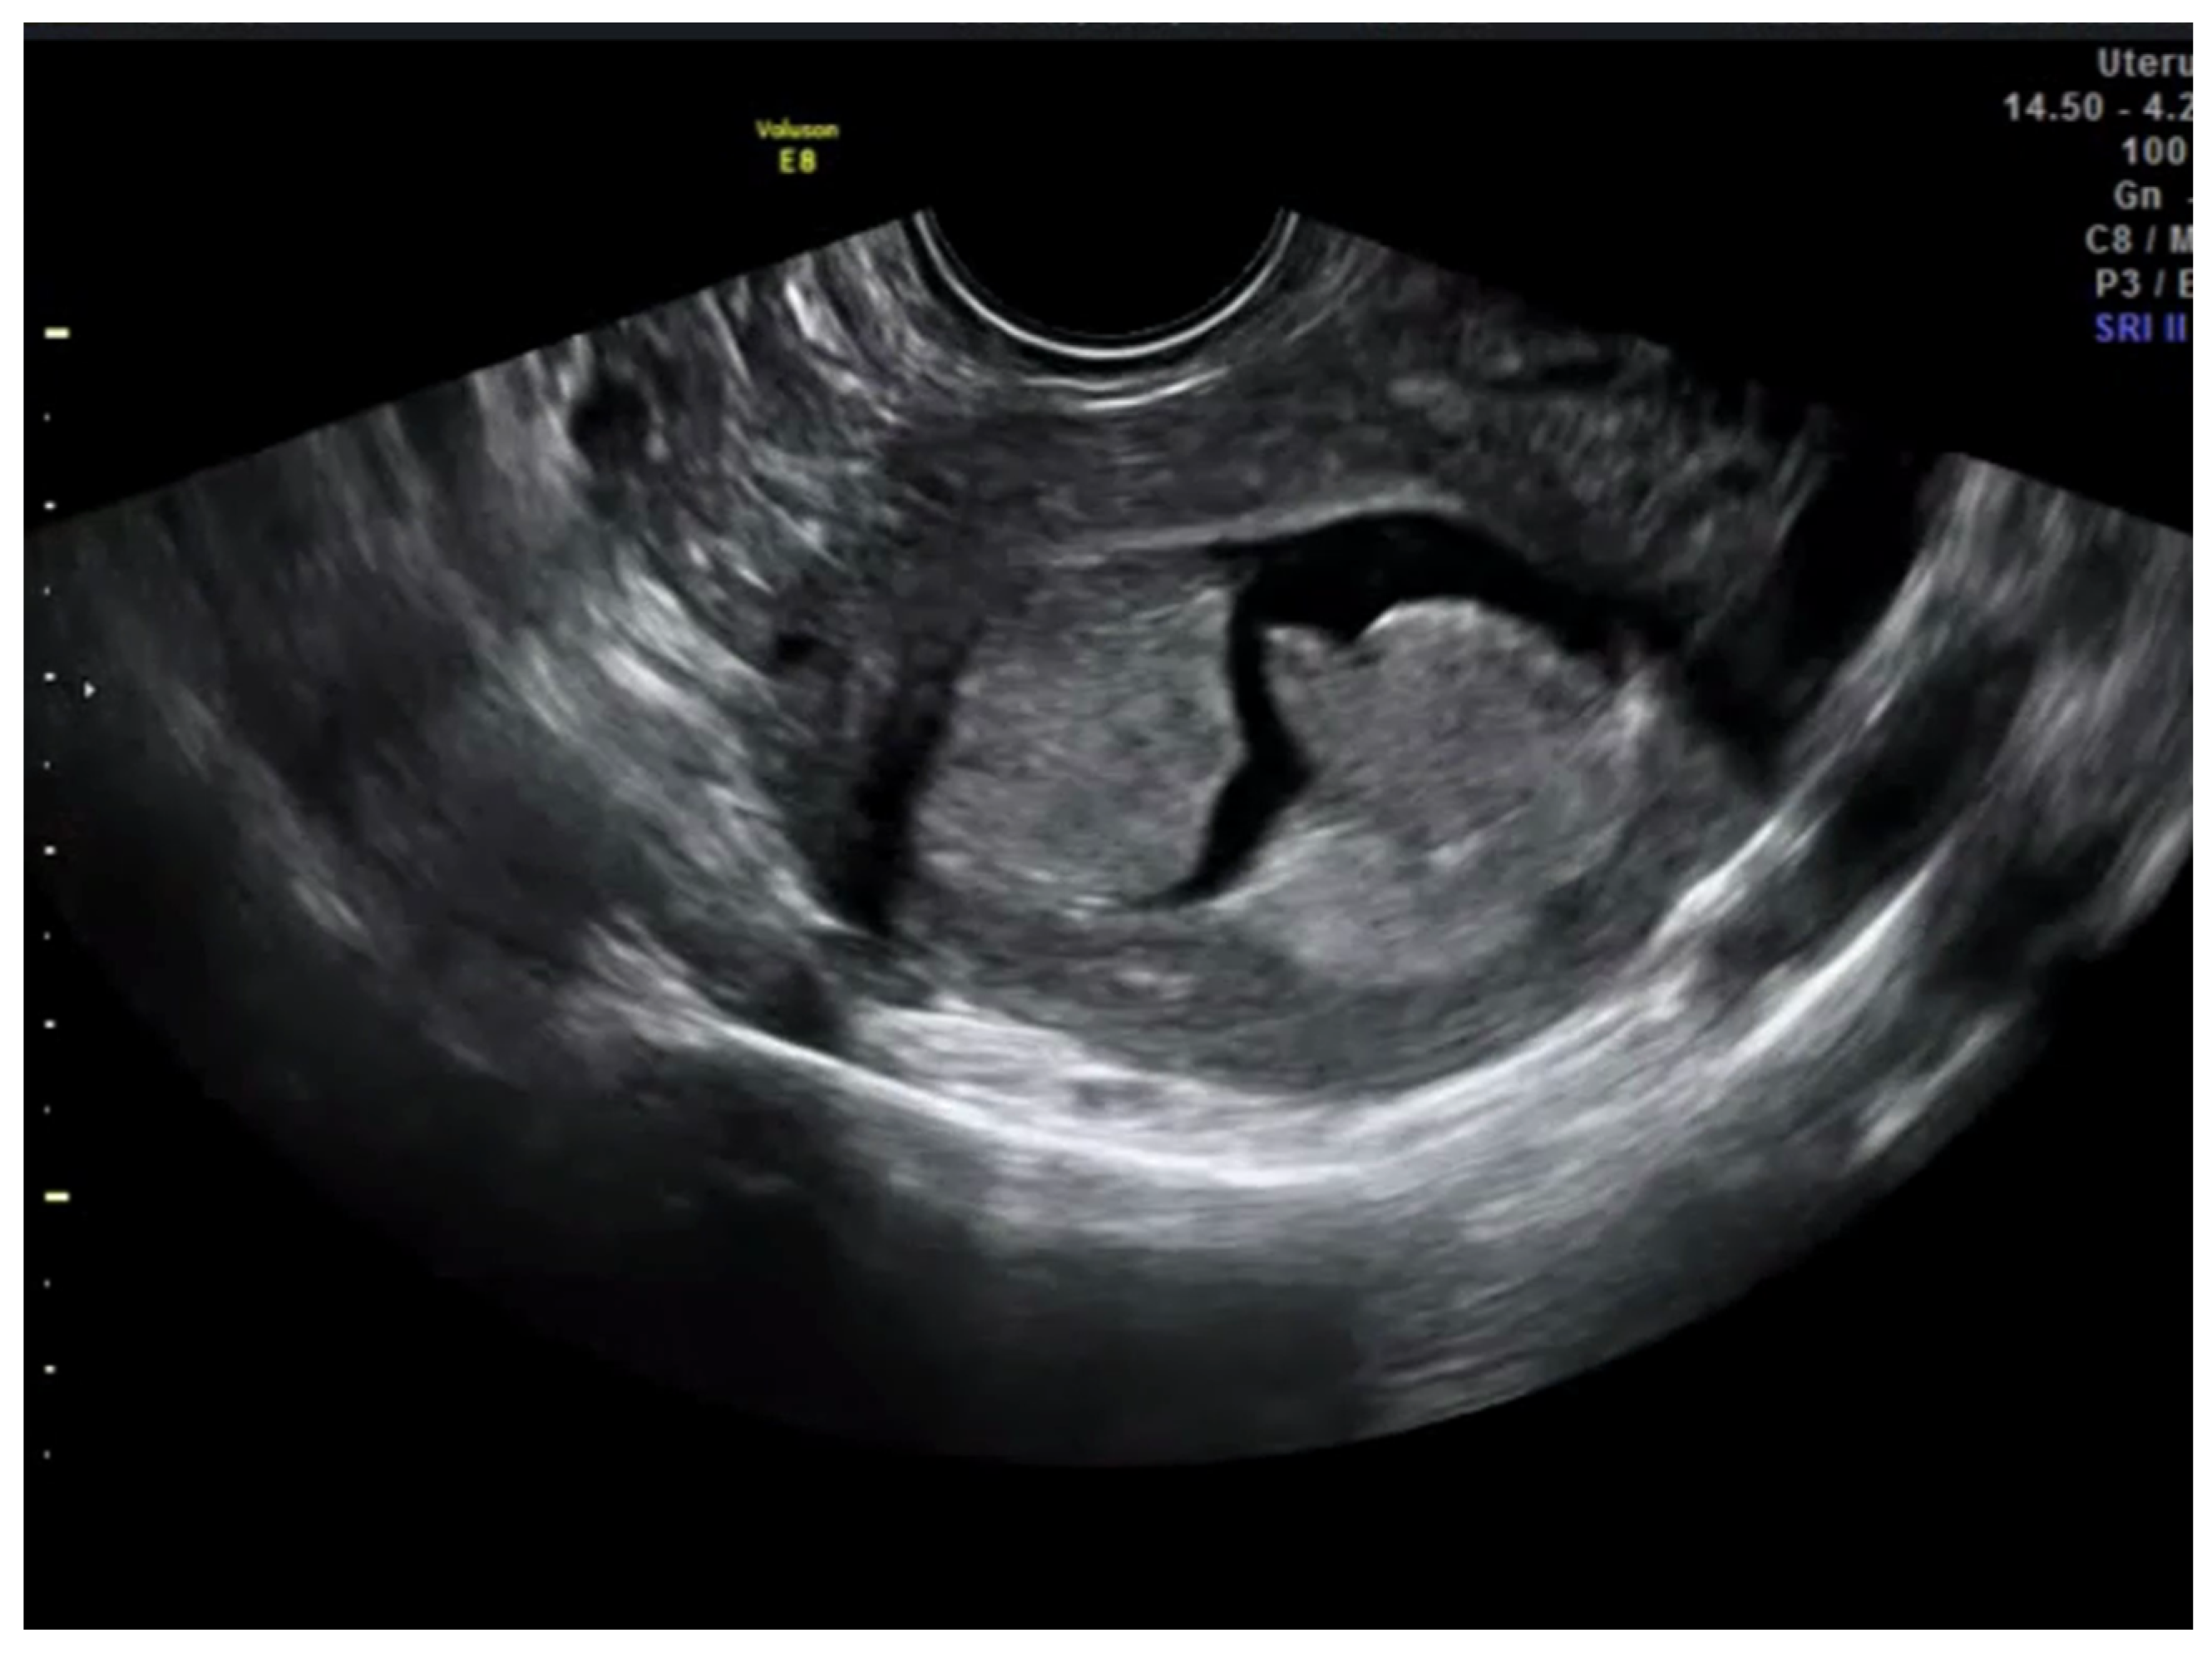

Finally, in the Karlsson’s approach, the ratio between the maximum anteroposterior diameter of the endometrial lesion and the uterine anteroposterior diameter, both measured in the sagittal plane, is estimated. Similar to the Gordon’s approach, if the ratio is <50%, myometrial invasion is estimated as less than half of the myometrium; in contrast, if the ratio is >50%, it is classified as more than half of the myometrium (Figure 2).

Figure 2. Transvaginal ultrasound showing a case of superficial infiltration in endometrial cancer using the Karlsson’s method. The ratio endometrial thickness/uterine anteroposterior diameter was 25.3%.